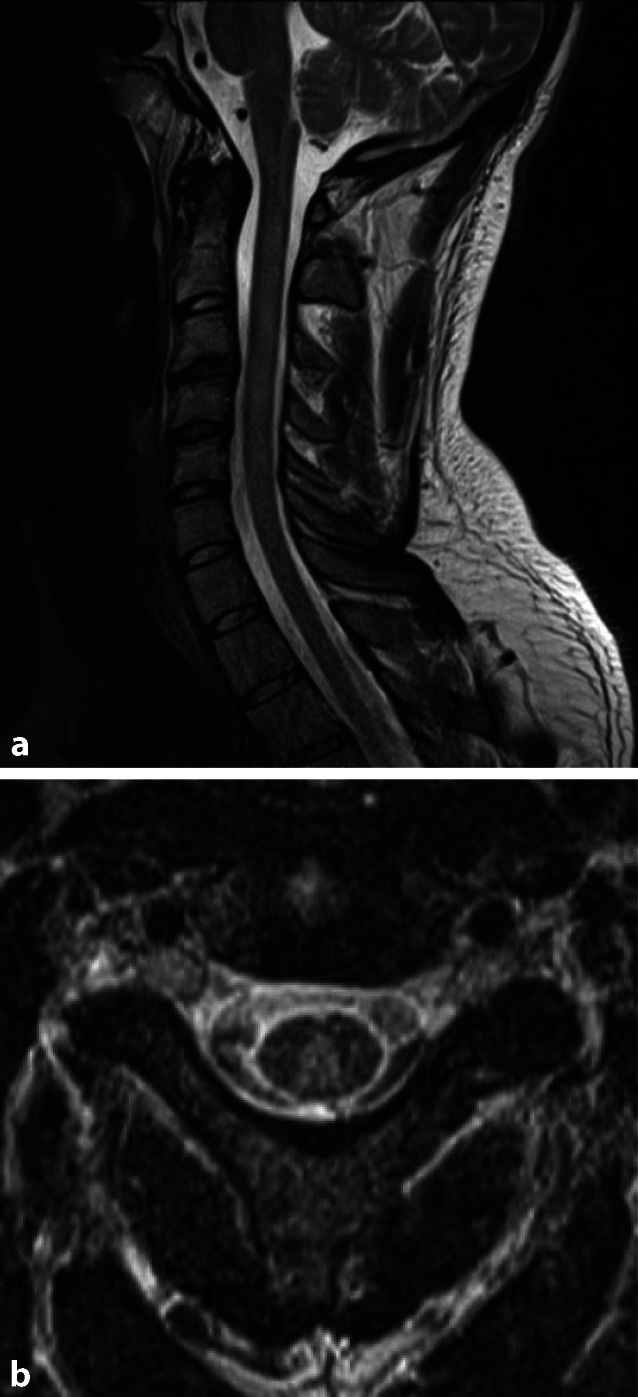

B12- und Kupfermangel

Ein B12- und Kupfermangel präsentiert sich als subakute progressive Myelopathie. Sie manifestiert sich bildmorphologisch in der Columna dorsalis des Rückenmarks mit einer bilateralen symmetrischen Signalsteigerung in der T2w, die keine Kontrastmittelaffinität aufweist (Abb. 3). Primär ist das Zervikal- und Thorakalmark betroffen.